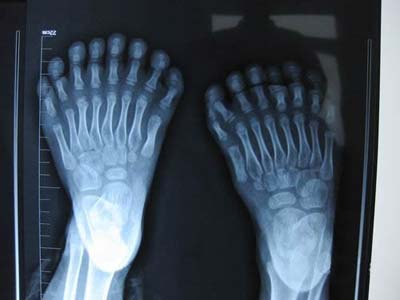

31根手指、脚趾“与生俱来”

鹏鹏的手指和脚趾长得“很特别”,小鹏鹏的手指有15根,脚趾有16根,加起来就是31根,令人奇怪的是,他的每只脚上都长有8根脚趾,且长得还很匀称,散开看酷似“莲花掌”,而手指长得就更奇了,有散开长的,还有并着长在一起的,一只手长有7根,另一只是8根。

盛京医院手足显微外科主任田立杰是省内有名的手外科专家,走南闯北见过的世面多了,但面对这么多、且复杂的手指、脚趾也是吃惊不小。“小鹏鹏得的是一种‘多指(趾)并指症’,虽然医学上很常见,但一般都是多一根,也就是常说的‘六指’。但像他这样多出这么多手指、脚趾的还是第一次看到。”

资料显示,印度22岁的小伙子哈拉姆,手指长了12根,脚趾有16根(有的是并着长的),但后来一位13岁的印度小孩子“刷新”了这一记录:12根手指、13根脚趾,全是分开长的。然而不管是并着算,还是分开算,鹏鹏确实是目前世界上手指和脚趾长得最多的人。

“手术需要4至5小时,最难的是两手,其中,要再造一个‘虎口’,左手三个并指还要切掉中间的一根,创面还要修复好……相对来说,脚趾的手术简单、容易一些,要将每只脚最外侧多余的三个脚趾切掉,然后修复好脚掌,让他和正常人一样!”